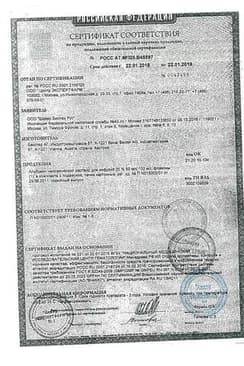

Сертификаты